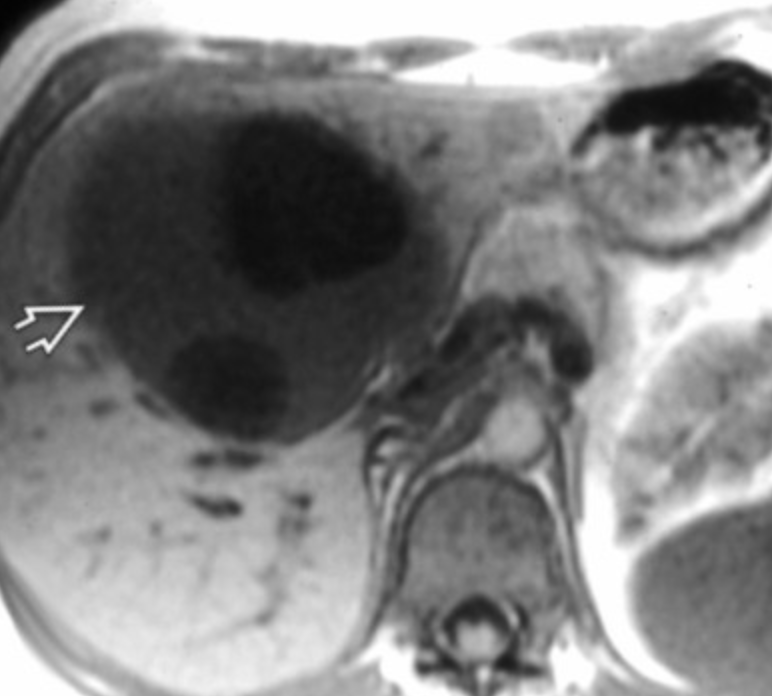

Biliary Cystadenocarcinoma

• Multiseptate liver mass

• Proteinacous fluid content better seen on MR than CT (see different signal on MR not seen on CT basically)

• Cannot really be differentiated fro biliary cystadenoma on imaging alone

• Nodularity of septa suggests malignancy